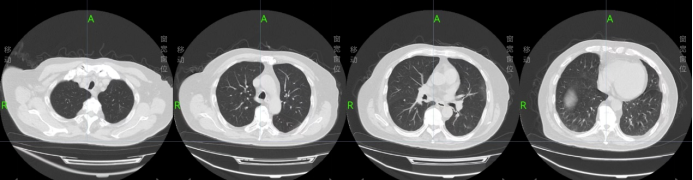

治疗过程中患者病情逐渐稳定可间断面罩吸氧过度为鼻导管吸氧,于2022年11月28日复查胸CT(图3)。病情逐渐稳定,待核酸转阴计划予以出院。

图片

图3  2022年11月28日胸部CT